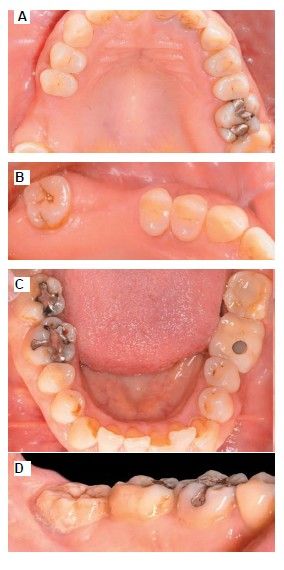

The medical history revealed no relevant medical or surgical antecedents, no known drug allergies, and no harmful habits. Intraoral examination revealed the absence of 1.6 and 1.7, and the presence of 1.8 and 4.8 (Figure 1). Radiographic examination using cone beam computed tomography (CBCT) revealed a residual height of 5.0 mm at 1.6, where an implant could be placed simultaneously, and 2.6 mm in the region of 1.7, making simultaneous implant placement with the lateral approach sinus elevation difficult (Figure 2).